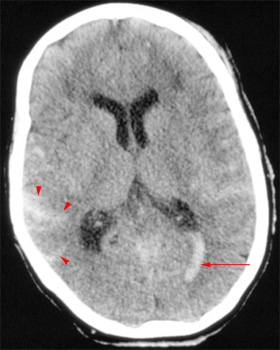

Intraventricular

hemorrhage (arrow) found in a trauma

patient. Note the subarachnoid hemorrhage in the

sulci in the subarachnoid space (arrowheads). |